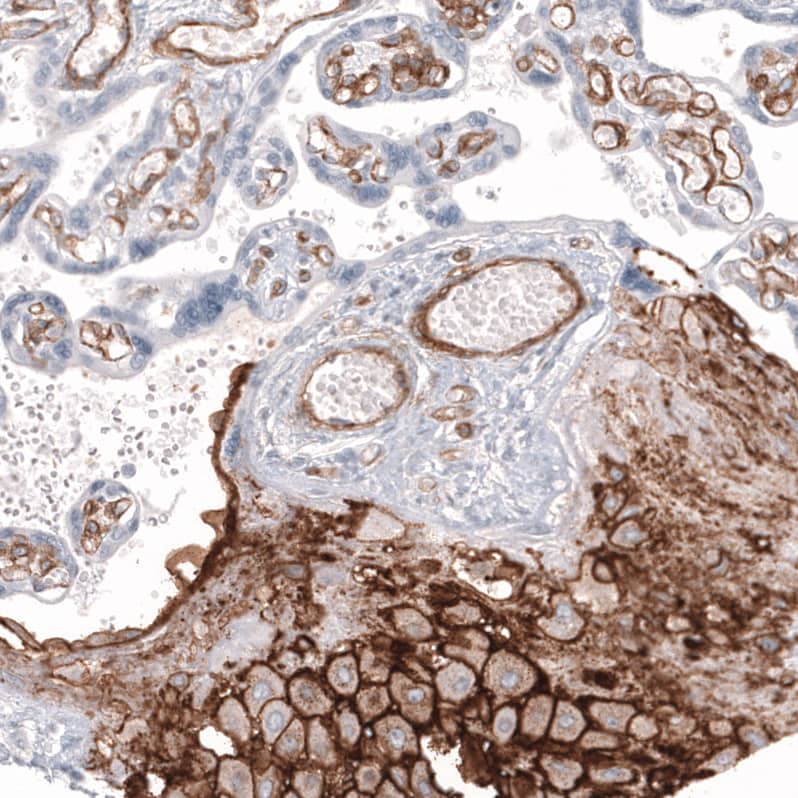

Staining of human placenta shows strong membranous positivity in decidual cells, as well as positivity in endothelial cells.